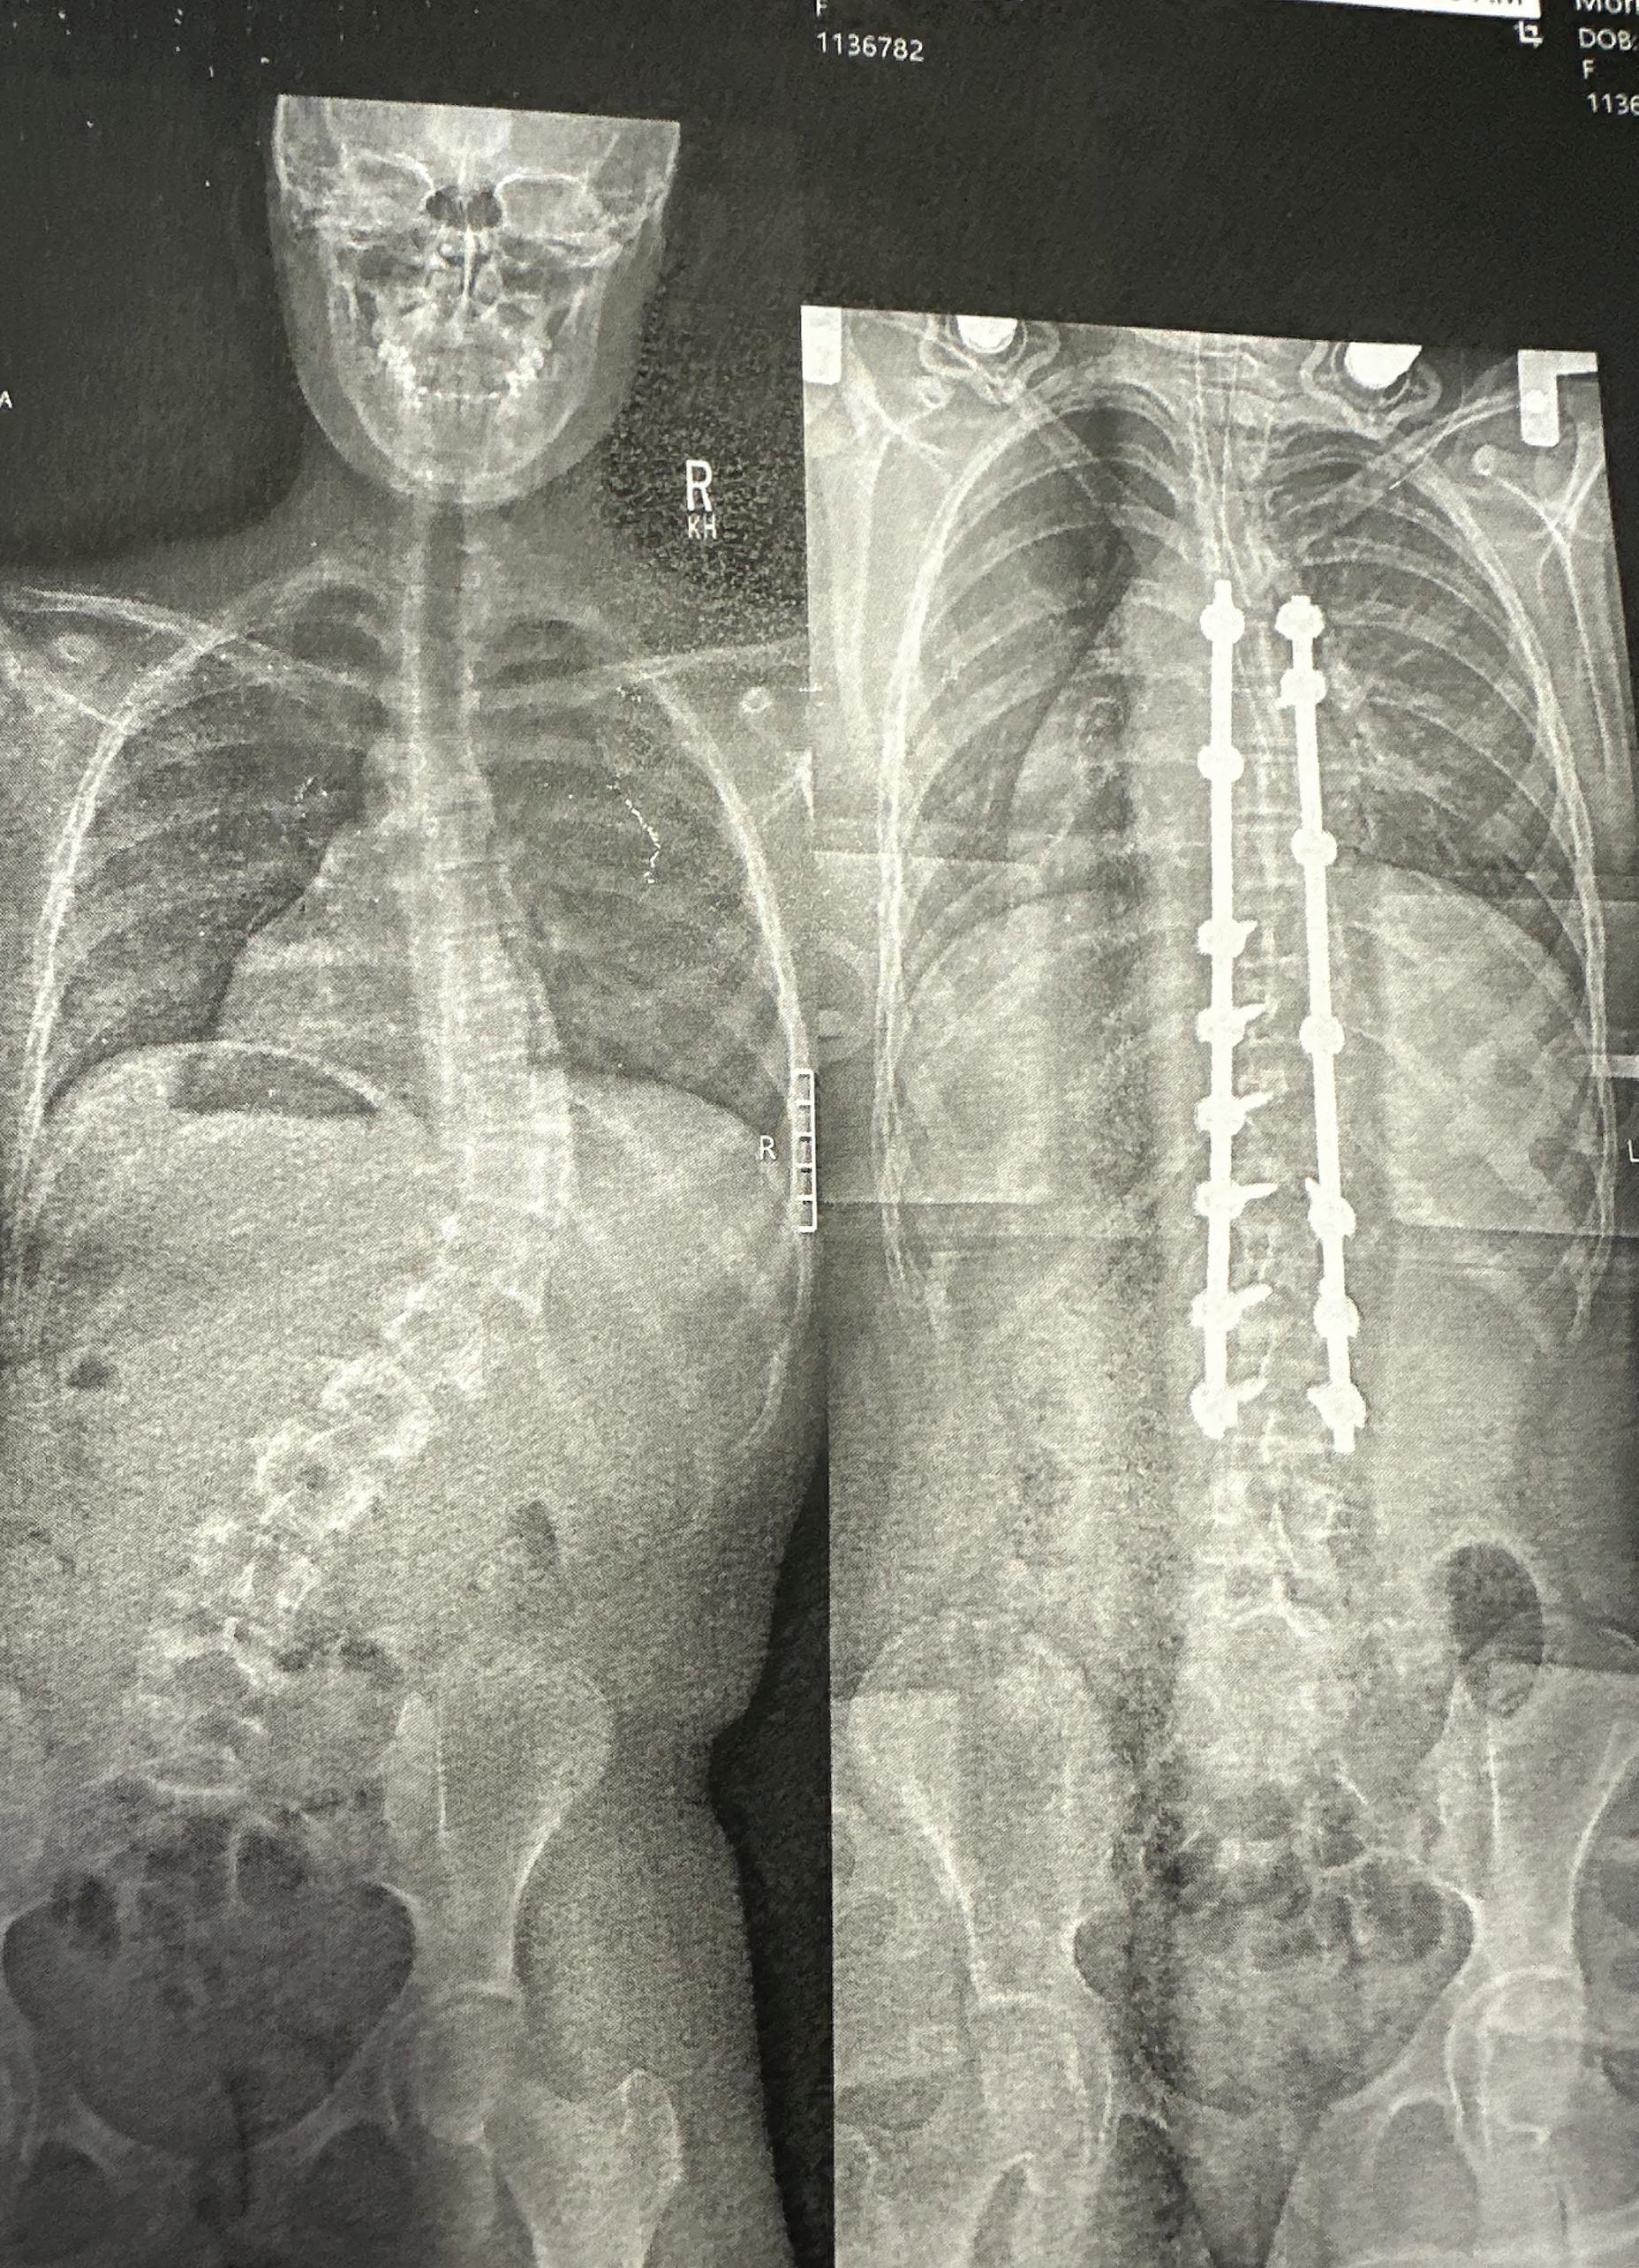

Senior Riley Morrison rolls out of bed at 4 a.m., straps on her weighted vest and embarks on her 20-mile morning run. For some, this regimen may seem extreme, but for Morrison, her upcoming marathon training requires sharp discipline and focus. After a major scoliosis surgery to fix a 60-degree curve in her spine, Morrison believed that running a marathon, let alone returning to athletics, would be impossible.

Morrison first began running in January 2024, after she had scoliosis surgery. Morrison was

told that after surgery, she wouldn’t be allowed to play any sports for six months to a year, holding her back from playing lacrosse and cheer.

According to the American Association of Neurological Surgeons, 3 percent of the population in the United States suffers from scoliosis. Retired Assistant-Chief of Orthopedic Surgery at Scottish Rite Hospital, Dr. Charles Johnston, helped create some of the revolutionary technology that enabled Morrison to recover quickly.

“In the 1980s, the typical scoliosis operation was not done as efficiently; it had greater blood loss and much more dissection, making it harder to recover from,” Johnston said. “But the instruments were improved, and as a result, you could get a better correction, and it was more reliable. The biggest

improvement that was made was that the patients didn't have to wear something externally after the surgery.”

Morrison was able to participate in the Dallas HalfMarathon on Feb. 23, running 13.1 miles alongside her dad in one hour and 57 minutes. Almost two years post-surgery and a few months out from her halfmarathon, Morrison is training harder than ever. Her commitment to marathon training, despite her surgery, has inspired outreach from hundreds, including Scottish Rite, which is sponsoring her marathon journey.

“I’m not surprised with a wellmotivated young lady like Riley that she is back to a significant activity level in a short period of time,” Johnston said. “In that 40-year period since 1980, the medical instruments really changed for the better. That’s why Riley is doing as well as she is and as active as she is.” Morrison’s rigorous running schedule often makes it hard to balance academics, school sports and college applications as a senior.